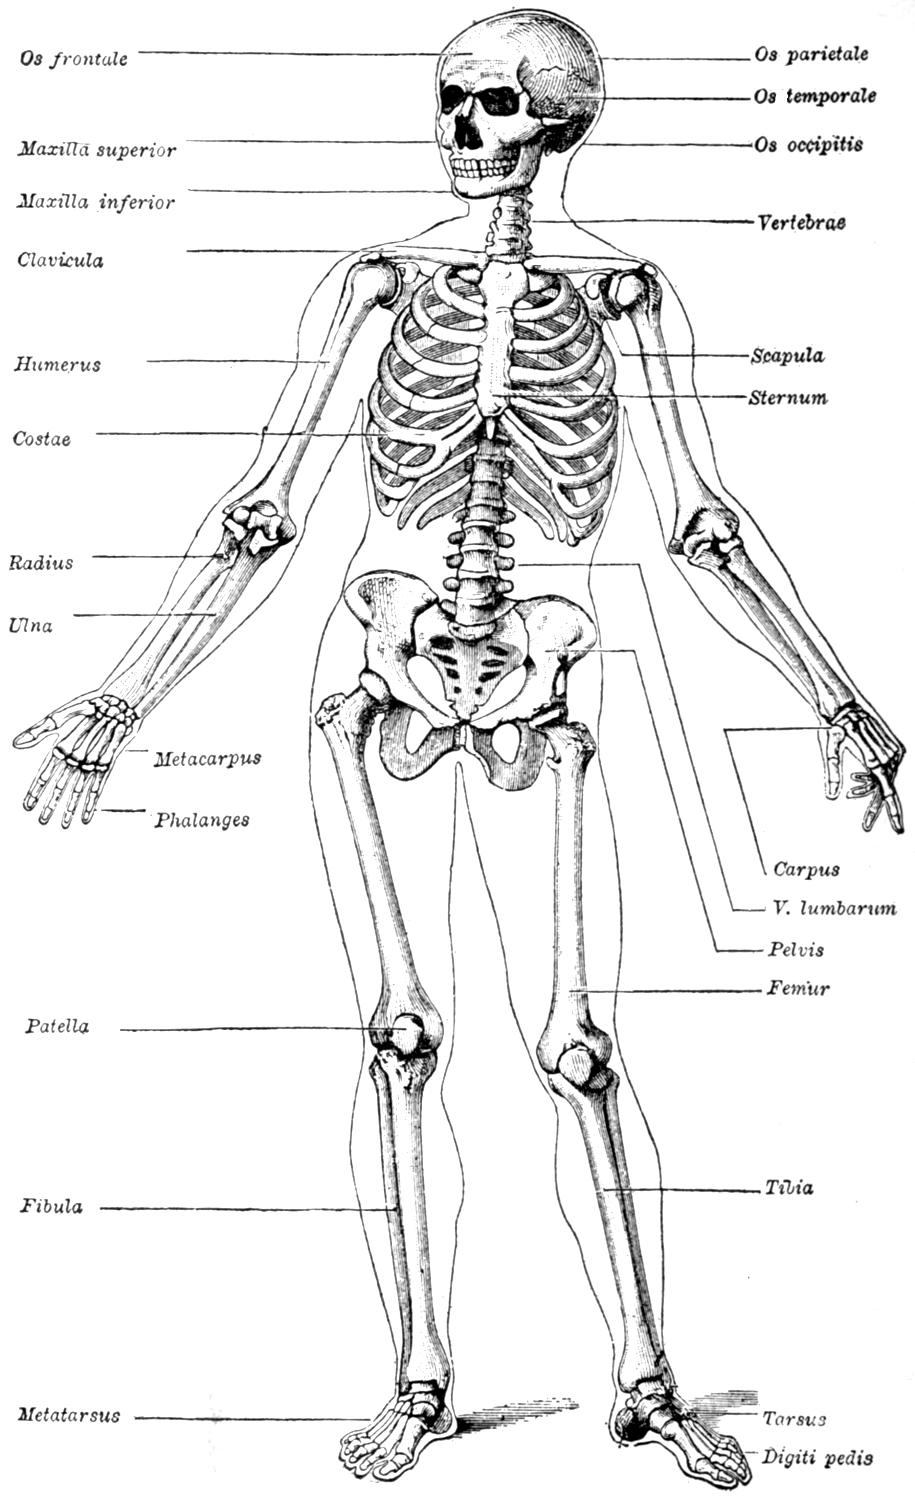

| III. | The Skeleton | H 28 |